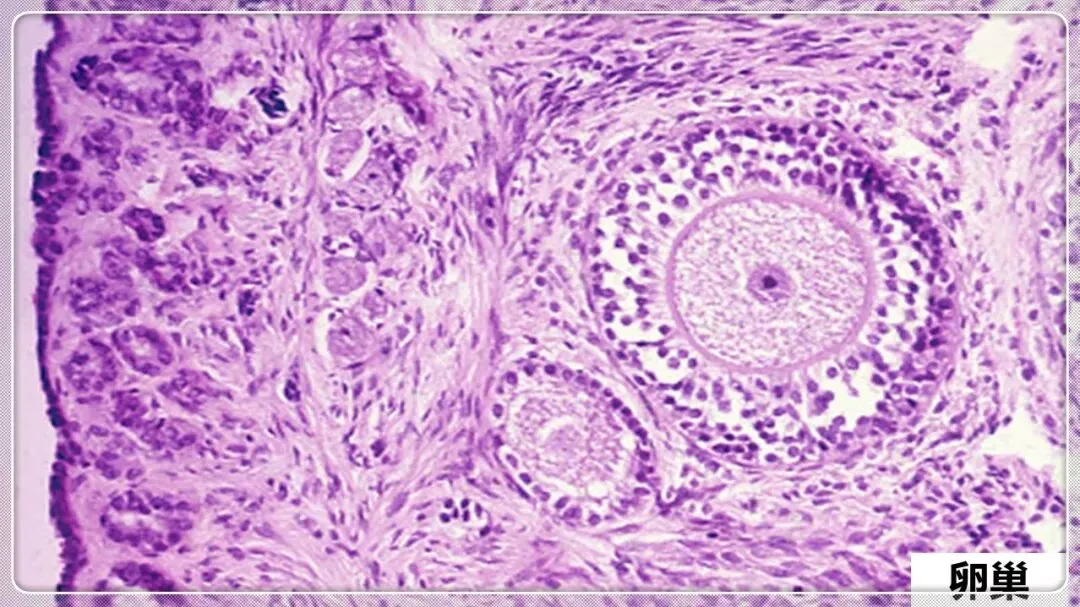

组织学与胚胎学笔记pdf【 常考图谱】

组织学与胚胎学 图谱